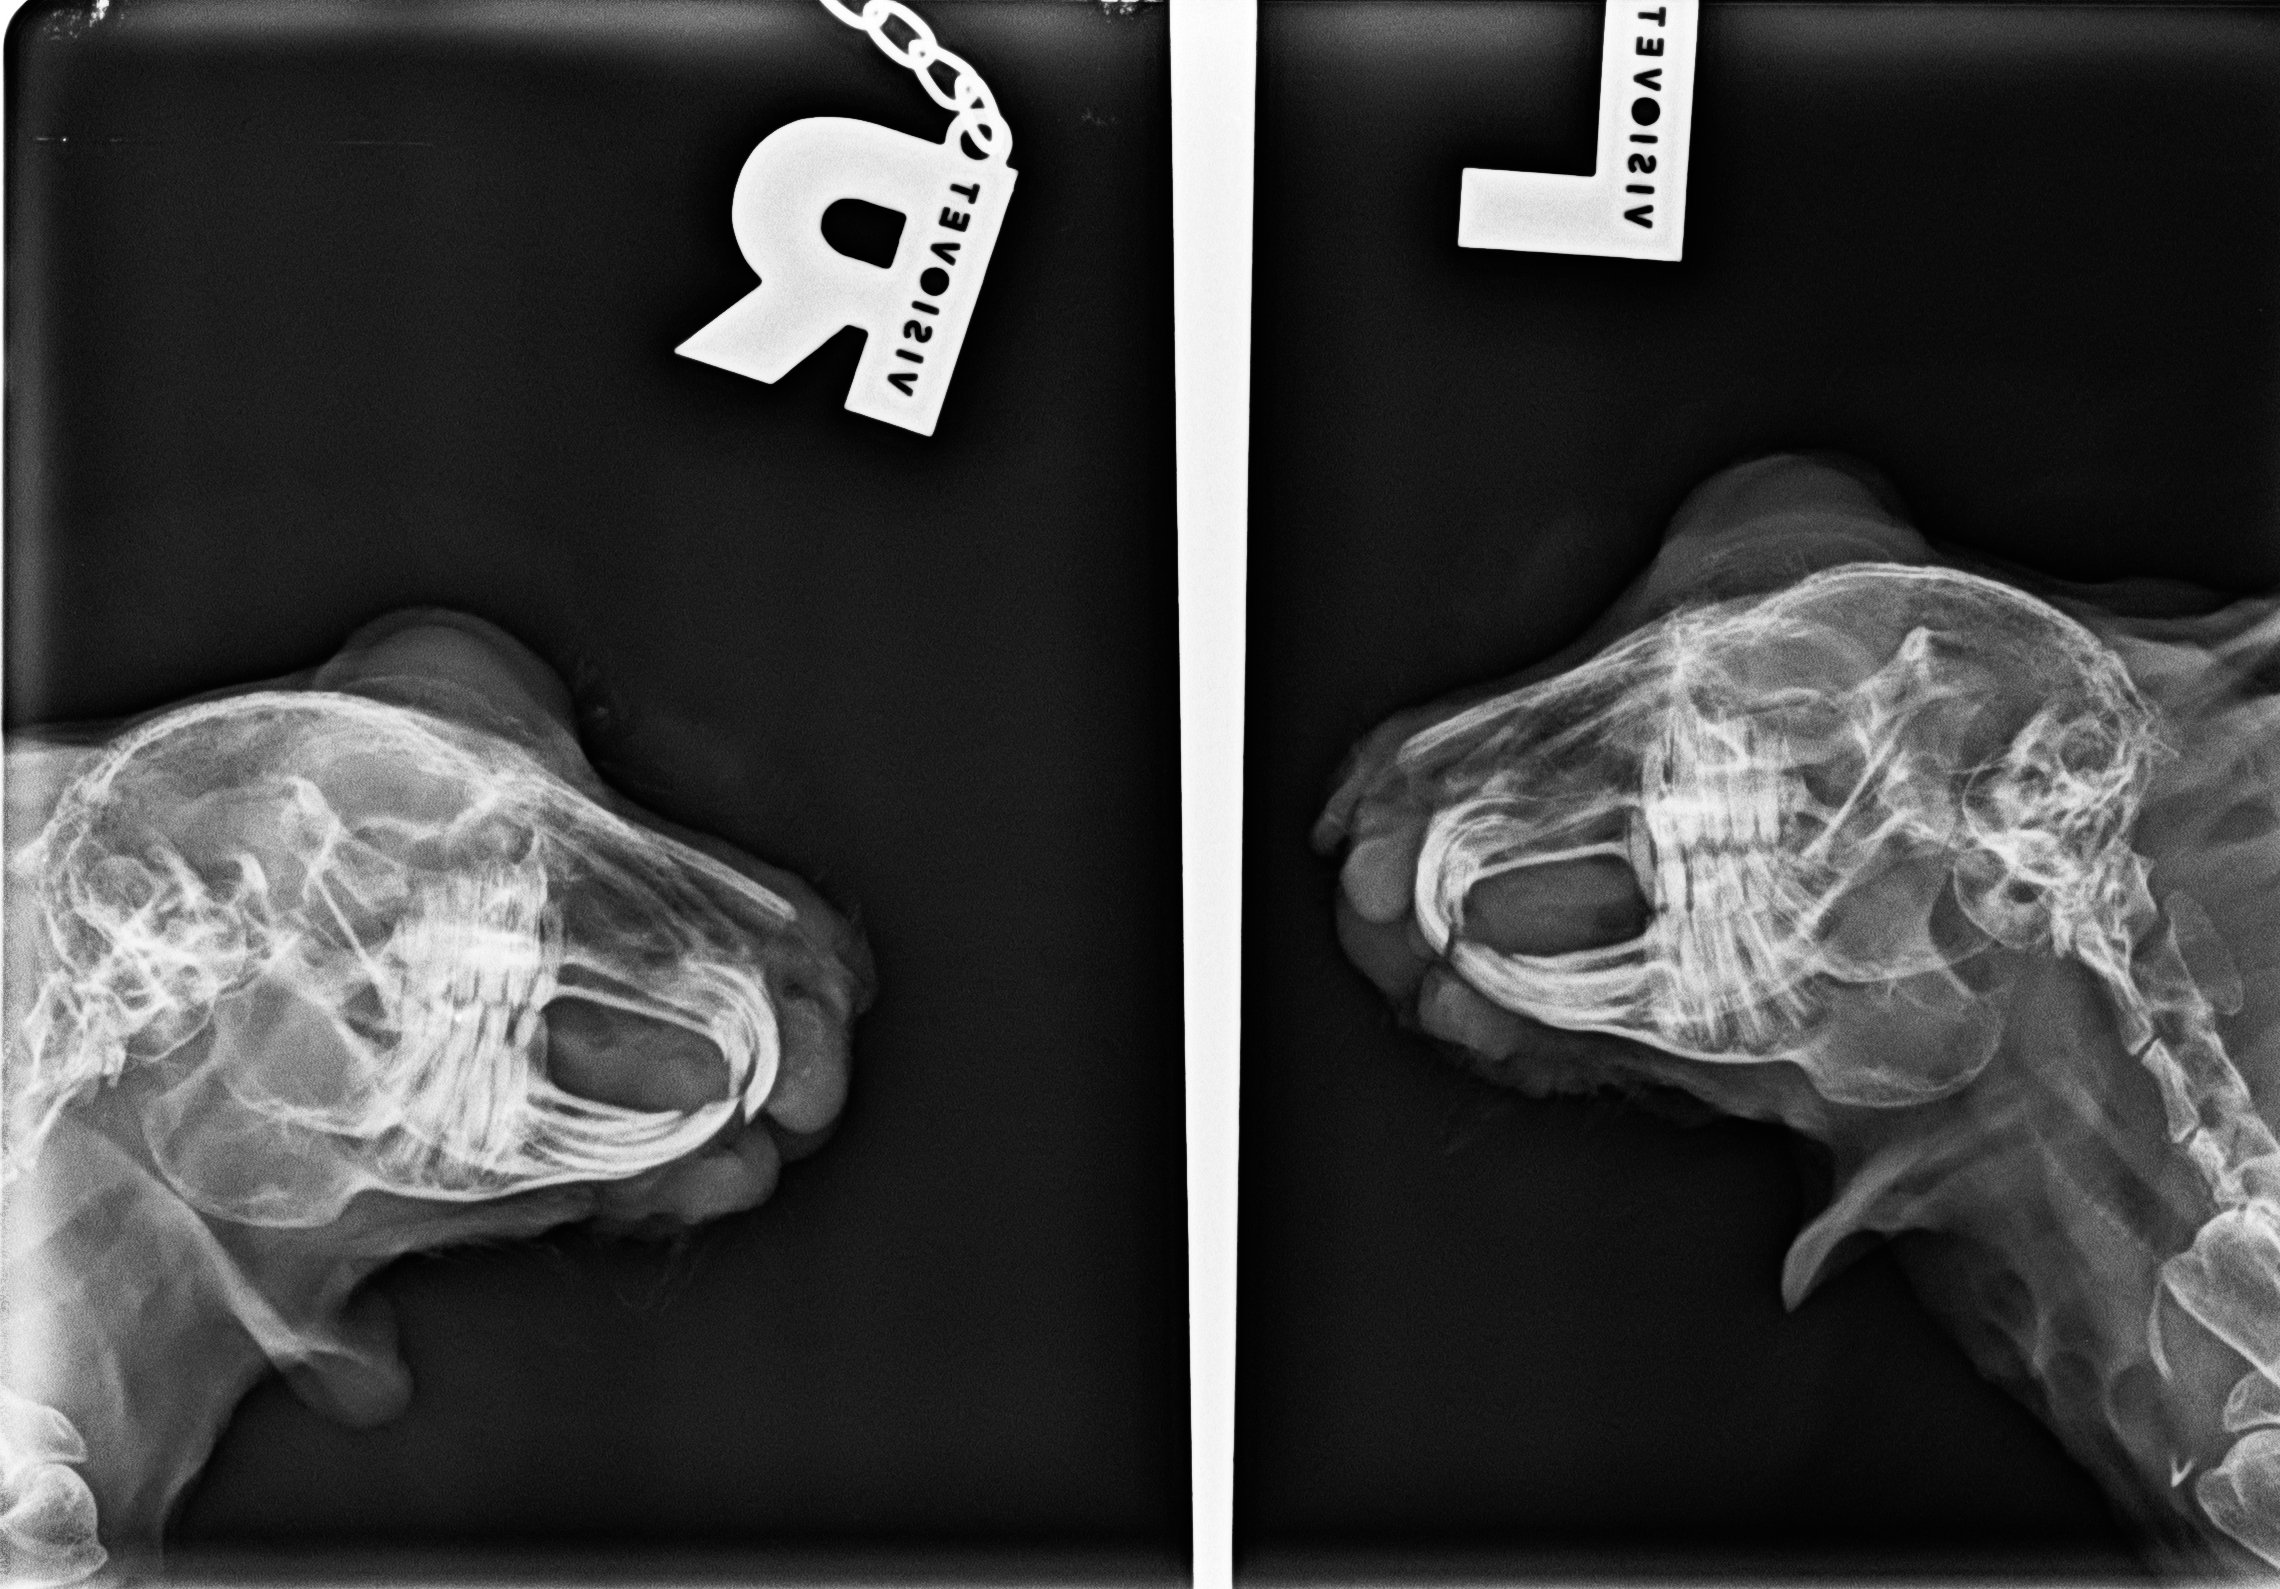

[PARENTDIR] Parent Directory - [IMG] Lea_Nager_Schädel_H..> 2025-08-07 16:02 2.1M [   ] Vetinf_Laborbefunde_..> 2024-07-12 14:55 156K